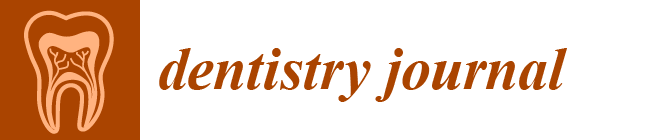

2.3. Surgical Procedures